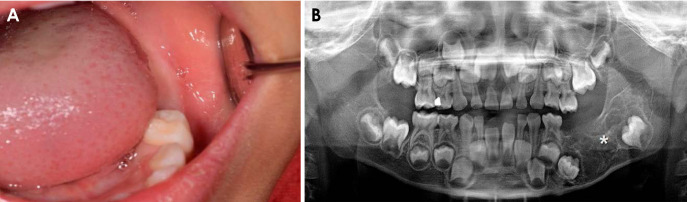

成釉细胞纤维牙本质瘤(AFD)是一种罕见的良性牙源性肿瘤,类似于牙本质发育不良的成釉细胞纤维瘤。本报告介绍了一例罕见的下颌骨纤维牙本质瘤病例,该病例为一名年轻患者,具有影像学特征。全景X光片和计算机断层扫描显示病变界限清晰,有内隔膜和钙化灶,导致相邻磨牙下移,颊舌侧皮质变薄,下颌后部扩张。手术通过肿块切除术切除了病灶,并在全身麻醉下拔除了患牙。在 5 年的随访期间,没有发现复发的迹象。AFD的放射学特征通常表现为中度到界限清楚的混合病变,具有不同程度的放射通透性,反映了牙本质形成的程度。当放射科医生在年轻患者的放射影像中发现多形性病变且几乎没有致密的放射通透性时,尤其是当病变伴有延迟萌出、嵌塞或缺失受累牙齿时,应将无牙颌畸形纳入鉴别诊断。

Ameloblastic fibrodentinoma (AFD) is a rare benign odontogenic tumor that resembles an ameloblastic fibroma with dysplastic dentin. This report presents a rare case of mandibular AFD with imaging features in a young patient. Panoramic radiography and computed tomography revealed a well-defined lesion with internal septa and calcified foci, causing inferior displacement of the adjacent molars as well as buccolingual cortical thinning and expansion of the posterior mandible. The lesion was surgically removed via mass excision, and the involved tooth was extracted under general anesthesia. During the 5-year follow-up period, no evidence of recurrence was observed. Radiologic features of AFD typically reveal a moderately to well-defined mixed lesion with varying degrees of radiopacity, reflecting the extent of dentin formation. Radiologists should consider AFD in the differential diagnosis when encountering a multilocular lesion with little dense radiopacity, particularly if it is associated with delayed eruption, impaction, or absence of involved teeth, on radiographic images of young patients.